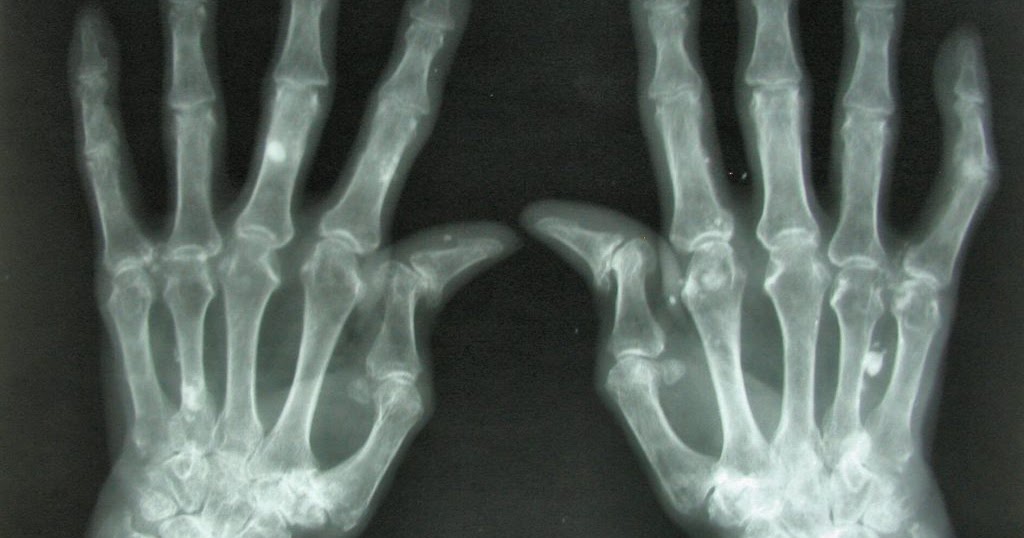

From rheumexamatlas.com

Rheumatoid Arthritis RheumExam Atlas Oranges And Rheumatoid Arthritis if you’re concerned about how inflammatory foods for rheumatoid arthritis are affecting your symptoms, talk to your doctor about. do oranges and other citrus fruits trigger rheumatoid arthritis (ra) flares? oranges, grapefruits, and limes are great sources of vitamin c, which boosts your immune system and fights. Research shows that getting the right amount of. We aimed. Oranges And Rheumatoid Arthritis.